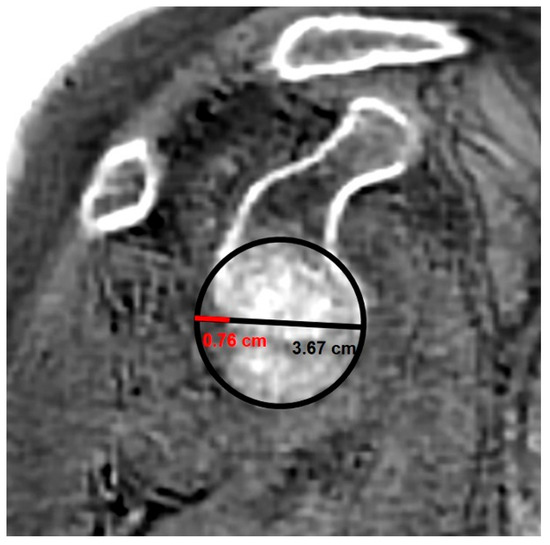

ZTE MRI for Rotator Cuff Tear Arthropathy: Integrated Bone–Muscle Analysis and Its Association with Pseudoparesis

by Engin Türkay Yılmaz, Serkan İbik, Vedat Yaman, Şeyda Betül Fındık, Üstün Aydıngöz and Gazi Huri

J. Clin. Med. 2025, 14(23), 8597; https://doi.org/10.3390/jcm14238597 - 4 Dec 2025

Background/Objectives: Evaluating glenoid changes in rotator cuff tear arthropathy (RCTA) is crucial for preoperative planning. MRI with zero echo time (ZTE) sequence, which produces CT-like images, allows for the assessment of osseous morphology as well as factors contributing to pseudoparesis in RCTA patients. [...] Read more.

Background/Objectives: Evaluating glenoid changes in rotator cuff tear arthropathy (RCTA) is crucial for preoperative planning. MRI with zero echo time (ZTE) sequence, which produces CT-like images, allows for the assessment of osseous morphology as well as factors contributing to pseudoparesis in RCTA patients. Methods: In this retrospective study, using 3T MRI, glenoid version, glenoid vault depth, humeral subluxation index, humeral head medialization, critical shoulder angle, glenoid best-fit circle width, glenoid best-fit circle bone loss ratio (GBLR), and anterior, central, and posterior glenoid bone loss were measured on reformatted 3D ZTE images in 43 shoulders independently by three observers. The same measurements were repeated by one observer after 10 days. Muscle cross-sectional areas were measured. Patients’ active ROMs, American Shoulder and Elbow Surgeons (ASES), and Constant–Murley scores were recorded. Patients unable to perform 90° forward elevation were classified as the pseudoparesis group. Results: Interobserver agreements were good to excellent, except for glenoid vault depth, anterior bone loss, and GBLR. Intraobserver agreements were good to excellent. The pseudoparesis group showed significantly less subscapularis muscle cross-sectional area (p = 0.006). Moderate correlations were found between subscapularis cross-sectional area and forward elevation, abduction, and internal rotation ([r = 0.471, p = 0.001]; [r = 0.447, p = 0.003]; [r = 0.464, p = 0.002], respectively). Moderate negative correlations were found between anterior glenoid loss and forward elevation (r = −0.411, p = 0.006) and abduction (r = −0.475, p = 0.001). Conclusions: MRI with ZTE sequence demonstrated good reliability for assessing osseous morphology in shoulders with RCTA. Glenoid anterior bone loss and loss of subscapularis muscle are both associated with pseudoparesis. Full article